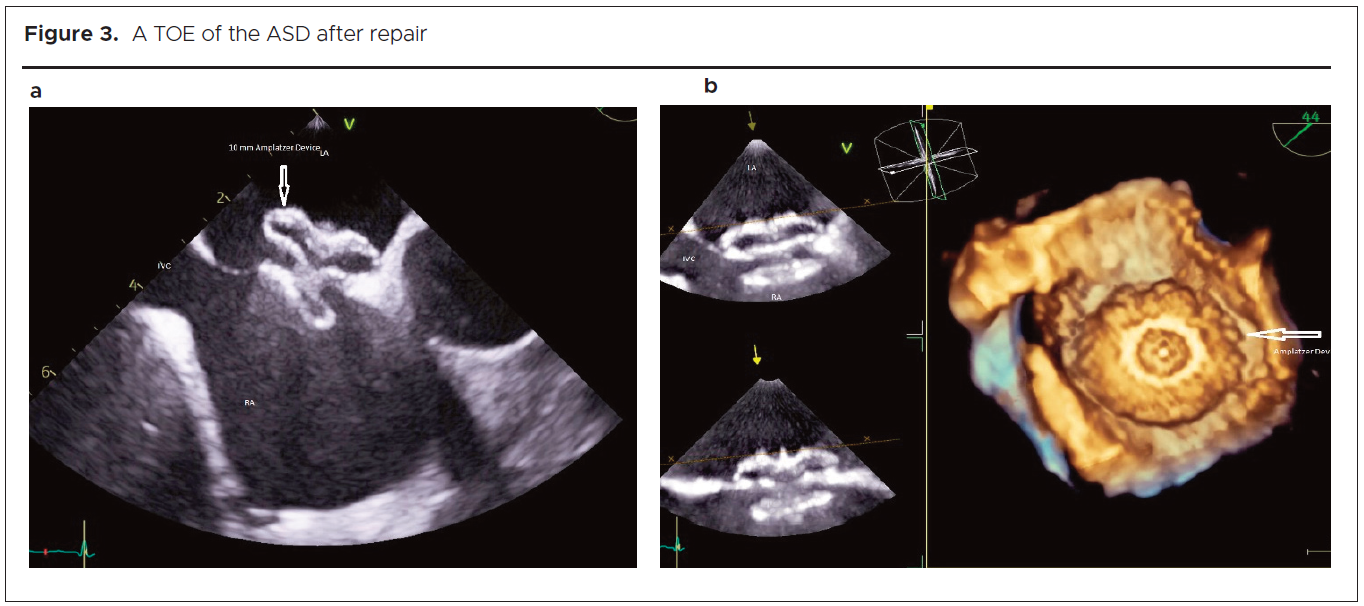

An arterial Duplex ultrasound identified subacute tight stenosis of the distal aorta, with occlusion of the right external iliac artery and right trifurcation. Computed tomography (CT) angiography demonstrated a small filling defect of the distal aortic arch, bilateral occlusions of the common iliac arteries (figure 1a), and occlusion of the right tibio-peroneal trunk.

1455-figures-1a-1b-2

Extensive thrombophilia screening did not identify any underlying predisposition to thrombosis, and no predisposing medications (such as oral contraceptive pill use) were implicated. A 24-hour cardiac tape demonstrated sinus tachycardia with no arrhythmias. Trans-oesophageal echocardiogram (TOE) revealed an asymptomatic secundum ASD (figure 1b), with left-to-right shunting and no associated risk factors. A diagnosis of paradoxical embolism causing bilateral arterial lower limb ischaemia, particularly affecting the right foot, was made. No viable options for revascularization were identified. She was managed medically with an unfractionated heparin infusion. This was switched to treatment dose subcutaneous dalteparin alongside warfarin until a target international normalised ratio of 2-3 was achieved. Lifelong anticoagulation and ASD closure were recommended, with cardiology follow-up scheduled. The patient was advised to contact the vascular team if she had any concerns relating to changes in her leg.

Clinical course

Six weeks later, while attending for a Monofer infusion for iron-deficiency anaemia, she reported to the medical day unit team that she had noticed some purple discolouration of the toes of her right foot. An urgent vascular review was arranged. Arterial Duplex ultrasound showed multiple occlusions in the lower limb arteries, characterised by monophasic waveforms and limited perfusion. She continued on anticoagulation. The case was discussed at the vascular multidisciplinary team (MDT) meeting, where it was agreed to prioritise closure of the ASD, given the absence of a clear indication for revascularisation at that stage. At her two-week vascular follow-up review, limb-threatening ischaemia was evident, with apical gangrene of the right second toe and hallux embolic patches (figures 2a and b). Toe pressures were absent bilaterally. The right ankle-brachial pressure index (ABPI) was too faint to assess, while the left measured 0.5, consistent with moderate arterial insufficiency.